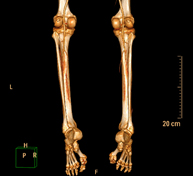

Exploració radiològica que mitjançant un sistema de raigs X i detectors que giren al voltant del pacient i que reconstrueixen les imatges per ordinador (TC Multidetector), permet l'estudi detallat dels ossos llargs (tíbia, peroné, fèmur, húmer, radi i cúbit). - Biòpsia òssia guiada per TC

Prova diagnòstica no invasiva que consisteix en l'estudi vascular del sector aorto-ilíac i dels vasos arterials d'ambdues extremitats inferiors i l'obtenció d'imatges d'alta definició anatòmica mitjançant l'ús d'un equip de TC Multidetector d'última generació i de contrast iodat. La qualitat de les imatges permet realitzar reconstruccions en 2D i 3D gràcies a estacions de treball especialitzades en l'estudi arterial.

Prova diagnòstica no invasiva que consisteix en l'estudi de vascular del sector aorto-ílíac i dels vasos arterials d'ambdues extremitats inferiors amb l'obtenció d'imatges d'alta definició anatòmica mitjançant l'ús d'un equip de TC (Tomografia Computaritzada) i contrast iodat. La qualitat de les imatges permet realitzar reconstruccions en 2D i 3D gràcies a estacions de treball especialitzades en l'estudi arterial.